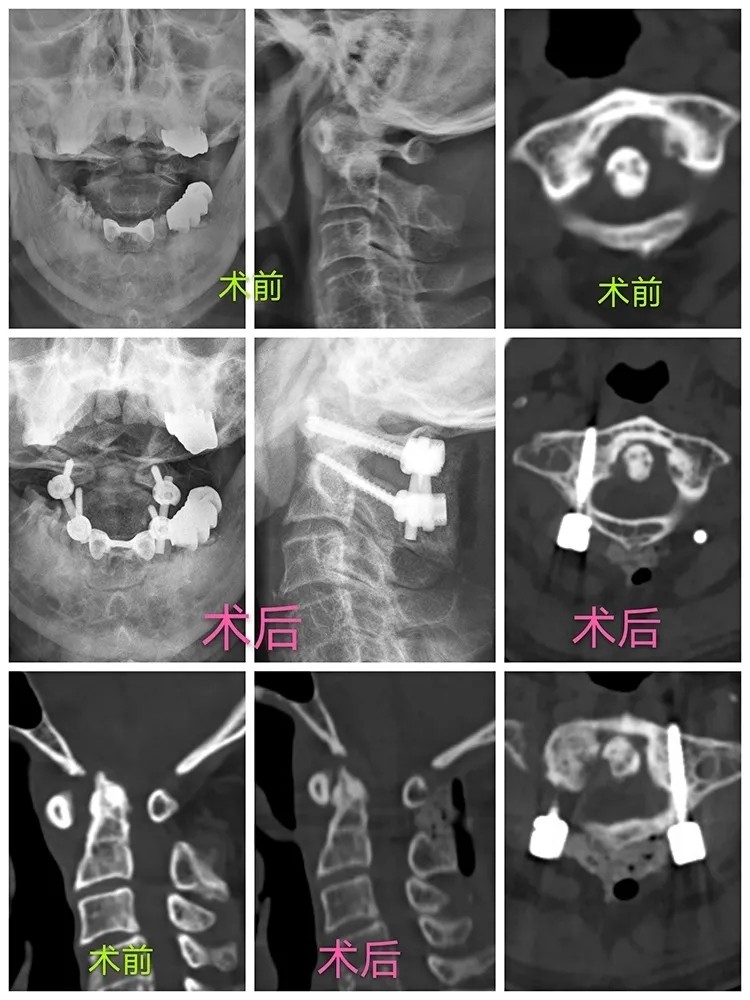

Not long ago, the Affiliated Hospital of Putian University had finished decompression and fusion combined with percutaneous pedicle screw fixation for lumbar spinal stenosis, which is the first surgery that performed under the assistance of the “Tianji” surgical robot and 3D microscope in China. Recently, with the help of the same technical equipment, the hospital also finished an operation on an elderly patient with serious cervical vertebra problems, which include atlantoaxial dislocation, upper cervical myelopathy and high-riding left vertebral artery. This is another spearheaded robot-assisted surgery performed in the hospital.

After taking a careful consideration into his medical history, physical examination and the imaging results, Prof. Lin confirmed his diagnosis that the patient had several cervical vertebra problems, including atlantoaxial dislocation, upper cervical myelopathy and high-riding left vertebral artery, so he recommended that a surgery should be performed as soon as possible. When it came to design the operative plan, there were two factors that need to be considered. One was that the patient is already 80 years old, and the other was that he had high-riding left vertebral artery with the vertebral artery dominance, which may result in a higher risk of vascular injury if a screw is used, and may further cause serious complications such as cerebral infarction or even death after surgery. After considerable discussion, the team of Prof. Lin decided to perform the surgery by following three steps: firstly, performing gradually great weight skull traction for positioning the dislocated cervical vertebra under general anesthesia; secondly, precisely inserting the screws with the help of “Tianji” surgical robot; thirdly, decompressing under 3D microscope that enables a high-definition visualization of the process.

The surgery lasted for less than 90 minutes and the peri-operative blood loss was about 70ml. During the surgery, the screws were well distributed so that the relocation of the atlanto-axial joint, and the decompression were all fully realized. The patient's symptoms were greatly relieved and his neck pain disappeared completely after the surgery, and the patient could walk freely with the neck brace on the first day after the surgery. He said gratefully with his thumbs up to Prof. Lin, "I haven't had such a good sleep for a long time, thank you very much!"